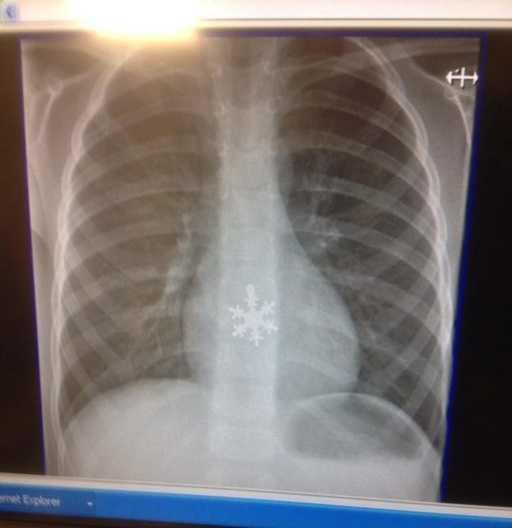

10. 「我朋友的儿子吞了雪花?」

一些奇怪的X光照片,看完整个人都不好了……-10.jpg